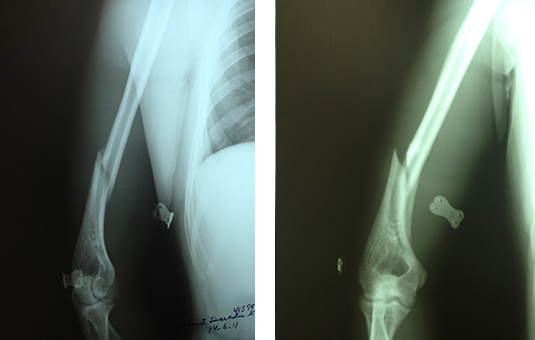

CORRECCIÓN DE AFLOJAMIENTO DE PRÓTESIS 1.PRÓTESIS AFLOJAMIENTO E INFECCIÓN DE VARIOS AÑOS. 2. RETIRO DE LA PRÓTESIS Y COLOCACIÓN DE PERLAS DE ANTIBIÓTICO ENTREVISTA PROGRAMA VIDA ENTREVISTA BDP CANAL 5 ENTREVISTA PIE PLANO ENTREVISTA ZAPATOS CORRECTOS INFILTRACIÓN DE ÁCIDO HYALURONICO EN CADERA